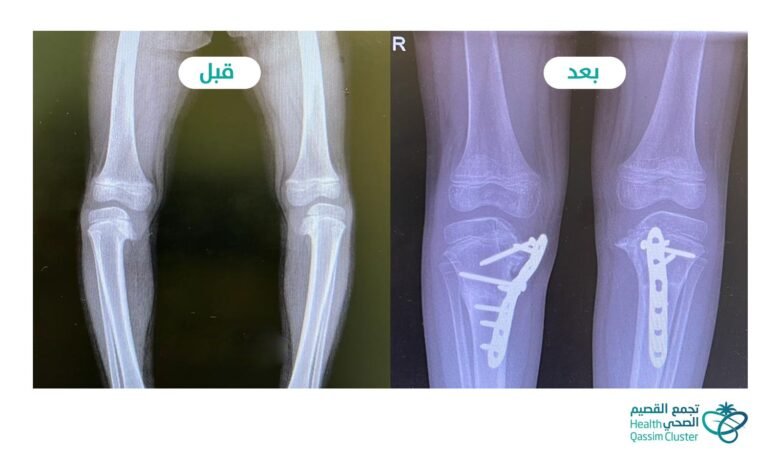

وأضاف: بعد إجراء التقييم السريري والفحوصات الإشعاعية والمخبرية اللازمة بينت إصابتها بمرض “داء بلاونت” ، وهي حالة مرضية يكون فيها عيب خلقي في غضاريف النمو لأعلى الساقين يؤدي إلى تقوس الساقين، وتزداد شدته مع نمو الشخص المصاب وتقدمه في العمر.

وعلى ضوء نتائج الكشف السريري والفحوصات الاشعاعية قرر الفريق المعالج إجراء عمل جراحي تمثل في إجراء قص عظمي تصحيحي مزدوج في كل ساق، وتثبيت العظام بشريحة معدنية ومسامير خاصة، حيث تم إجراء العمل الجراحي للساق اليمنى واليسرى في جلسة واحدة استغرقت أربع ساعات.

وبعد إجراء العملية الجراحية ومتابعة الطفلة من قبل الفريق الطبي والتمريضي وتحسن حالتها تمكنت من المغادرة إلى المنزل، واعطائها موعدًا للمتابعة في عيادة العظام، وبعد المتابعة تبيّن الالتحام التام لمكان القص العظمي واستقامة الساقين، واستطاعت الطفلة -ولله الحمد- المشي بشكل سليم دون عرج أو ميلان.